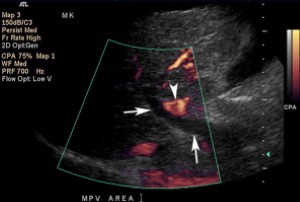

Khoảng 50% các bệnh nhân Budd-Chiari phát hiện tĩnh mạch thùy đuôi to với đường kính trên 3 mm, và dấu hiệu này được coi là đặc trưng khi không có suy tim (Hình 21) [25]. Tĩnh mạch này giãn là do thùy đuôi là thùy duy nhất trong gan dẫn lưu trực tiếp vào tĩnh mạch chủ dưới, và nó còn làm cầu nối tắt nhận máu của các nhánh bàng hệ trong nhu mô gan còn lại nên dẫn tới phì đại thùy đuôi và tĩnh mạch thùy đuôi [25].

Hình 21. Hội chứng Budd-Chiari ở bệnh nhân nam 30 tuổi có tiền sử hemoglobin niệu kịch phát về đêm và xuất hiện sưng phồng ổ bụng. (Hình A) Siêu âm màu phát hiện hẹp tĩnh mạch gan giữa với aliasing mầu gân chỗ nối của nó với tĩnh mạch chủ dưới (mũi tên). (Hình B) Ảnh siêu âm màu và Doppler cho thấy tĩnh mạch gan giữa thông, nhưng tốc độ dòng chảy tăng cao. (Hình C) Ảnh siêu âm màu cho thấy tĩnh mạch thùy đuôi to (mũi tên) tĩnh mạch của nó dẫn lưu trực tiếp vào tĩnh mạch chủ dưới. Hình ảnh cộng hưởng từ và sinh thiết gan xác định hội chứng Budd-Chiari.